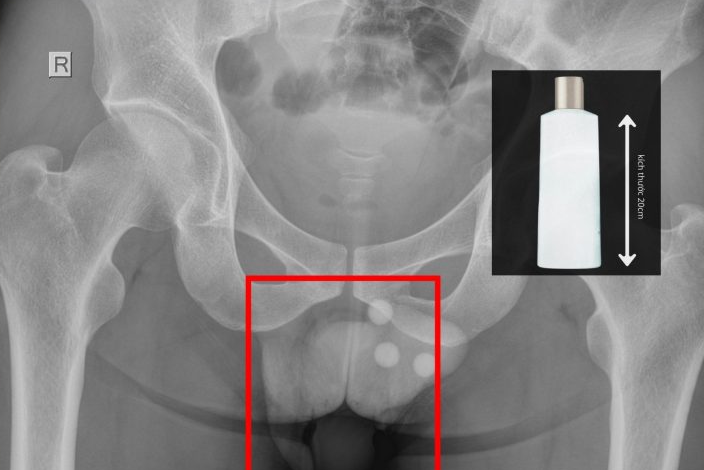

Ngày 8/3, bác sĩ chuyên khoa II Nguyễn Vũ An (chuyên khoa Ngoại tổng quát, tỉnh Tây Ninh) cho biết đơn vị vừa cấp cứu một người đàn ông nhập viện trong tình trạng đau rát dữ dội vùng hậu môn. Qua thăm khám, các bác sĩ phát hiện một chai nhựa dài khoảng 20cm mắc kẹt sâu trong trực tràng của người bệnh. Dị vật này tiềm ẩn nguy cơ gây thủng ruột và nhiễm trùng nặng nếu không được xử trí kịp thời.

Qua thăm khám và chụp X-quang, bác sĩ xác định dị vật nằm sâu trong trực tràng và không thể lấy ra bằng các thủ thuật thông thường. Ê-kíp đã tiến hành gây tê tủy sống, nong hậu môn và cẩn trọng lấy dị vật ra ngoài.